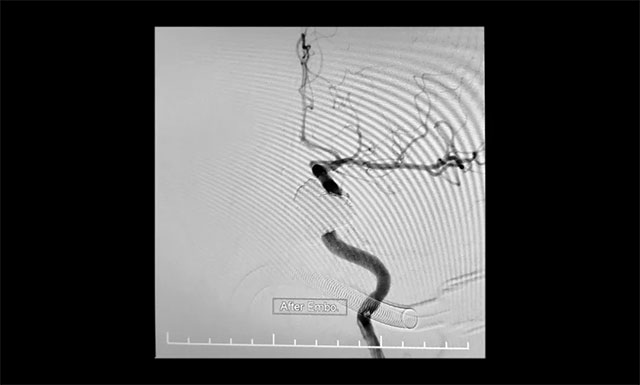

“鋼筋混凝土技術(shù)”操作時(shí)需十分謹(jǐn)慎,若注膠不足會(huì)導(dǎo)致瘺口封閉不全癥狀不緩解,而注膠不慎又會(huì)導(dǎo)致膠溢入頸內(nèi)動(dòng)脈,造成頸動(dòng)脈堵塞致大面積腦梗塞的災(zāi)難性后果。術(shù)中,張琪博士在李喆醫(yī)生、周林華醫(yī)生協(xié)助下先將海綿竇內(nèi)小心填入13枚大直徑彈簧圈作為“鋼筋骨架”,然后準(zhǔn)確地將球囊置于瘺口處的頸內(nèi)動(dòng)脈內(nèi),緩慢充盈球囊將瘺口暫時(shí)與頸內(nèi)動(dòng)脈隔離,然后小心翼翼地向瘺口內(nèi)注入onyx膠封堵,并仔細(xì)觀察膠的反流和擴(kuò)散情況。該方法每次球囊阻斷頸內(nèi)動(dòng)脈的時(shí)間不能超過(guò)6分鐘,否則將可能導(dǎo)致腦缺血。“1分鐘、2分鐘、3分鐘……”最終,經(jīng)過(guò)幾個(gè)循環(huán)的封堵,瘺口被栓塞得嚴(yán)嚴(yán)實(shí)實(shí),在確認(rèn)瘺口及主要異常回流途徑完全閉塞后,及時(shí)終止手術(shù),取得了較好的臨床效果,術(shù)中造影證實(shí)瘺口均完全閉塞。

術(shù)后,患者眼部腫脹緩解,眼球回縮。目前,患者正在康復(fù)中。

▲ 術(shù)中造影證實(shí)瘺口均完全閉塞